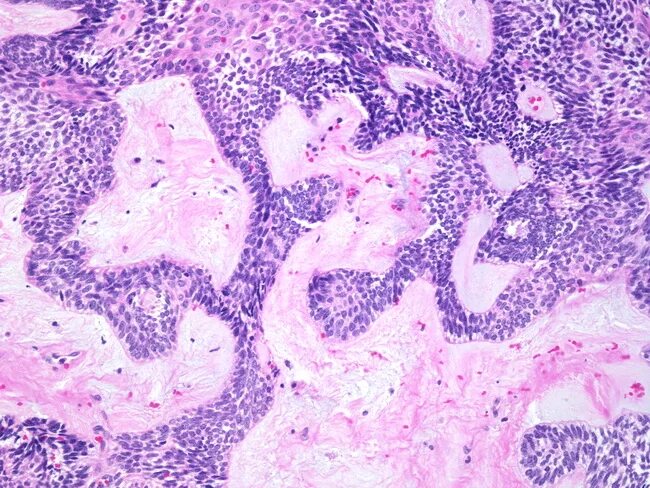

Гистология челюстей